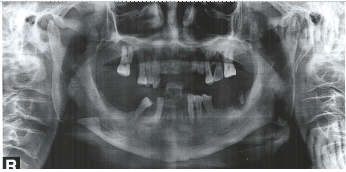

2016年11月13日曲面断层示:口腔内多颗牙齿缺失,分别为右上126、左上12、右下1247、左下1267,其中双侧上下切牙牙槽骨隐见牙槽窝,片中所示牙槽骨吸收明显,遗留牙齿的牙槽骨吸收均达根长的1/2以上。

2016年11月13日曲面断层(纸质图片)